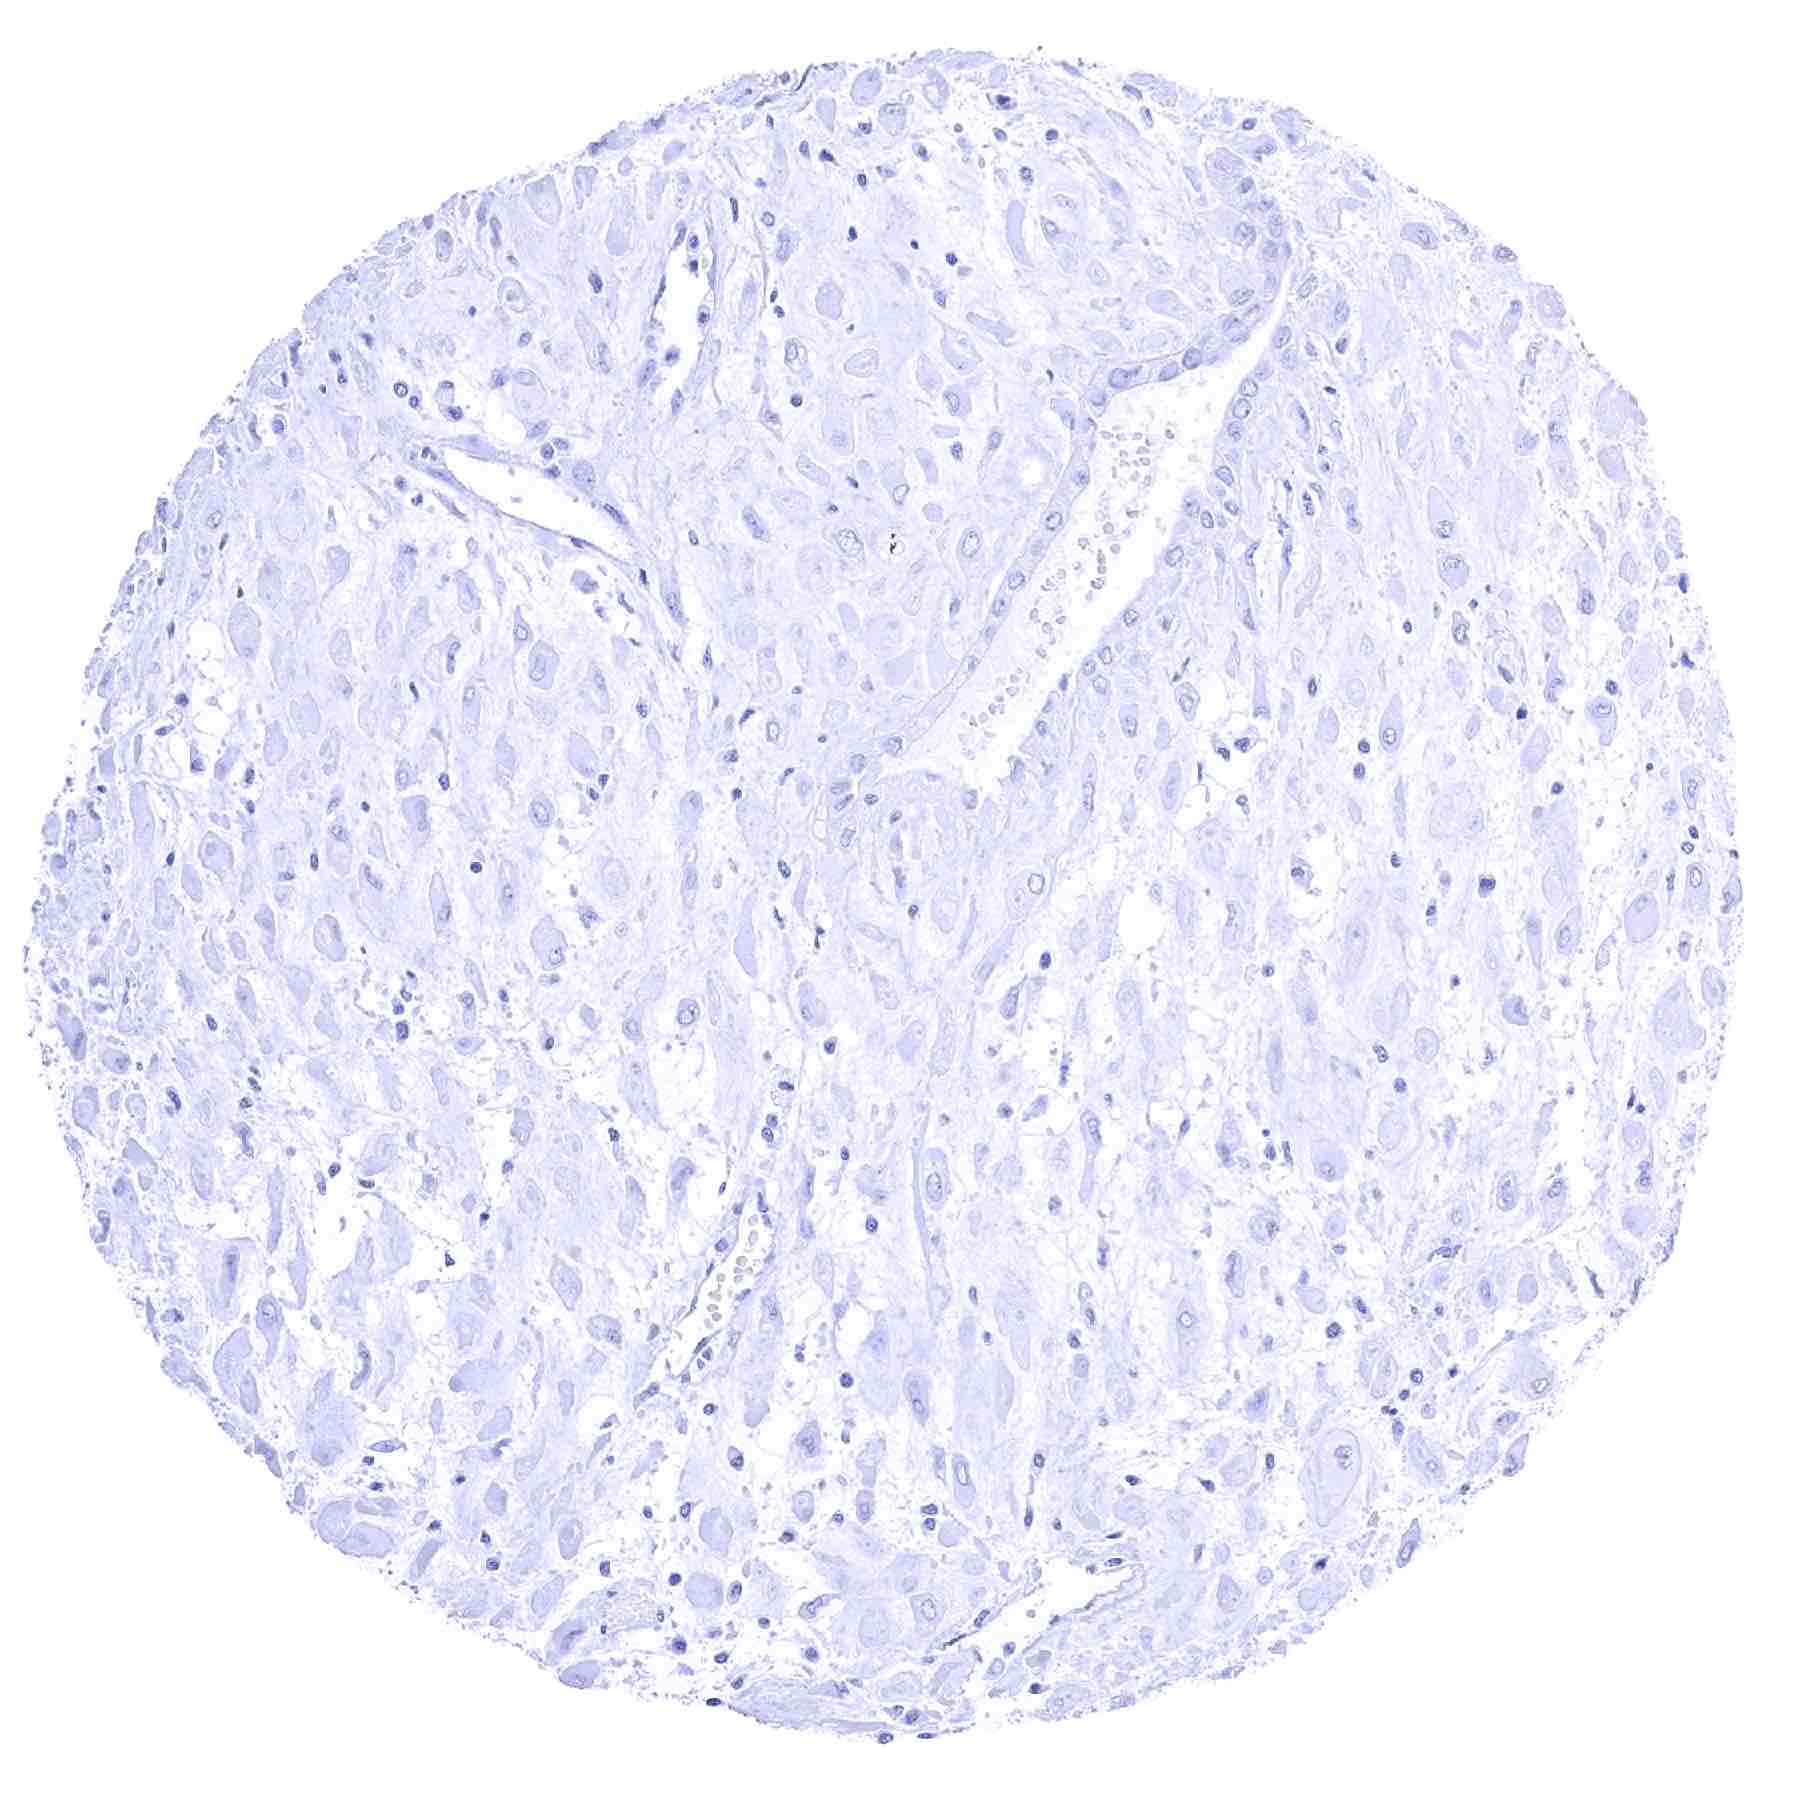

Uterus, ectocervix

Uterus, ectocervix (2)